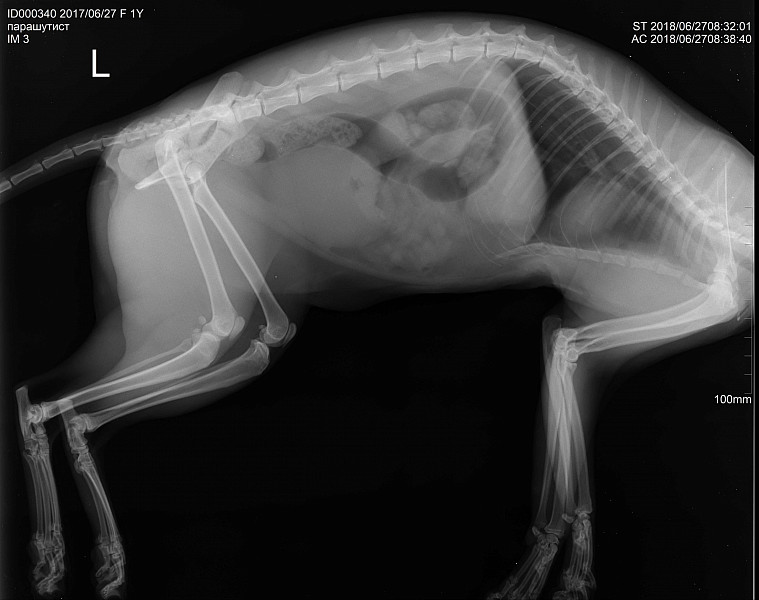

Заболевания позвоночника у домашних животных: диагностика и лечение

Раздел: Визуальные истории